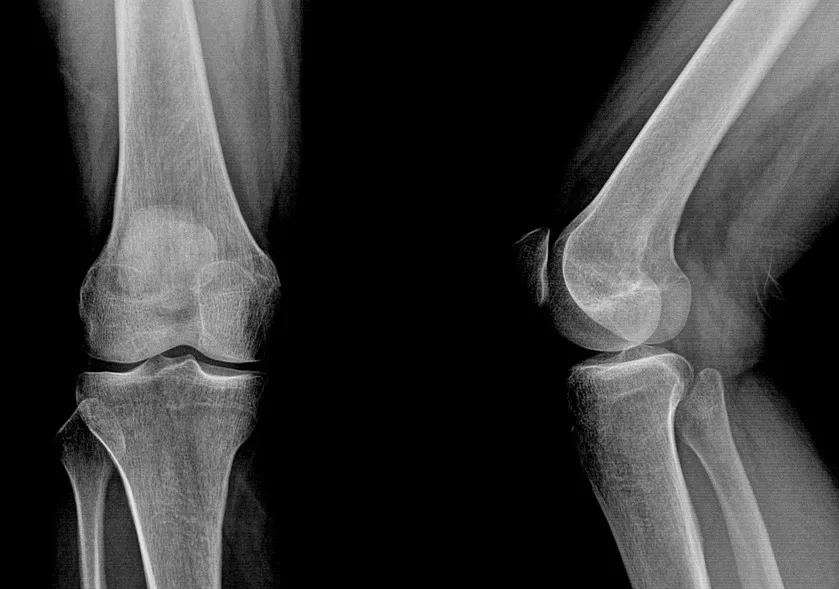

而膝关节几乎就是两个平面贴在一起

单靠骨头几乎没有稳定性

其稳定性全靠关节内外的韧带和肌肉

韧带,除非损伤,其稳定作用一般变化不大